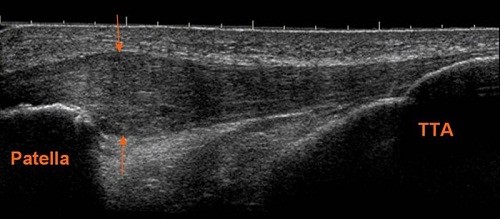

- Υπέρηχοι στο σύνολο των παθήσεων του μυοσκελετικού συστήματος (αρθρώσεις, τένοντες, μύες, σύνδεσμοι, κακώσεις, αθλιατρικές κακώσεις) και σε αρθρίτιδες (ρευματοειδής, αγκυλοποιητική, ψωριασική, αυτοάνοσα νοσήματα).